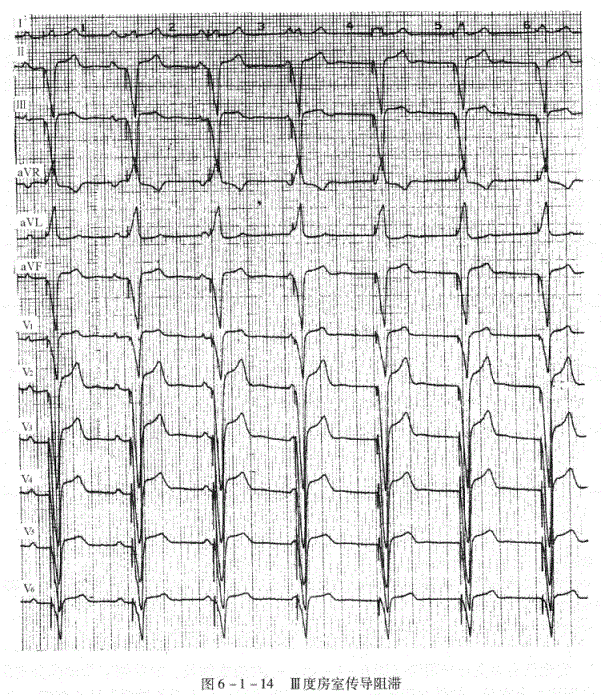

(三)Ⅲ度房室传导阻滞(图6-1-14)

1.P波与QRS波有各自的规律,互不相关,心房率快于心室率。

2.如阻滞发生于房室结,心室起搏点来自希氏束分支以上,则QRS正常,频率40~60次/分。

3.如阻滞发生于希氏束分支以下,心室起搏点来自心室内,.则QRS宽大畸形,频率20~40次/分。

临床资料:男性,71岁。临床诊断:冠心病、完全性房室阻滞。

心电图分析:窦性P波顺序出现,P-P周期匀齐,心房率60次/分。每个起搏脉冲信号之后均随之以心室起搏的QRS波群,起搏频率64次/分。QRS=140ms。心房与心室波群完全无关系。(这种右室起搏的波形除了I、aVR、aVL呈R型以外,其余均呈Qs型。此种波形在右室起搏中并不少见,可能与心脏顺钟向转位等因素

有关。)

心电图诊断:①窦性心律;②Ⅲ度房室阻滞;③心室起搏心律。